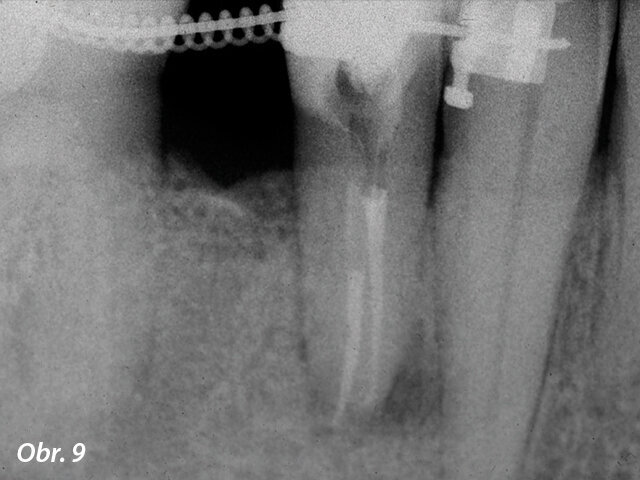

Situace byla zcela odlišná u dolního premoláru na obr. 7–9, kde si při absenci radiologických znaků léze, a i přes zdánlivě správný endodontický přístup jiného kolegy, pacient stěžoval na perzistentní bolest, která byla jak spontánní, tak vyvolaná poklepem. V tomto případě, kdy se zdála být předchozí léčba kořenových kanálků dobrá, by se jako vhodný mohl nabízet chirurgický přístup, který by v takovém případě mohl zajistit vyšší míru úspěšnosti než revize endodontického ošetření. Vzhledem k diagnostickým pochybnostem bylo rozhodnuto zhotovit 3D snímek, který odhalil endodontickou lézi způsobenou neošetřeným lingválním kanálkem. Tato správná diagnóza nám tedy umožnila provést selektivní intervenci na zbylé pulpě vedoucí k úspěšné léčbě neošetřeného kanálku.